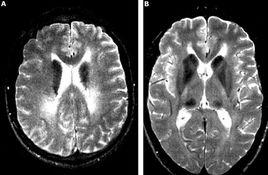

MRI檢查

可見腦基底核及部分灰質T2WI高信號,伴痴呆者可見雙側半卵圓中心區高信號。